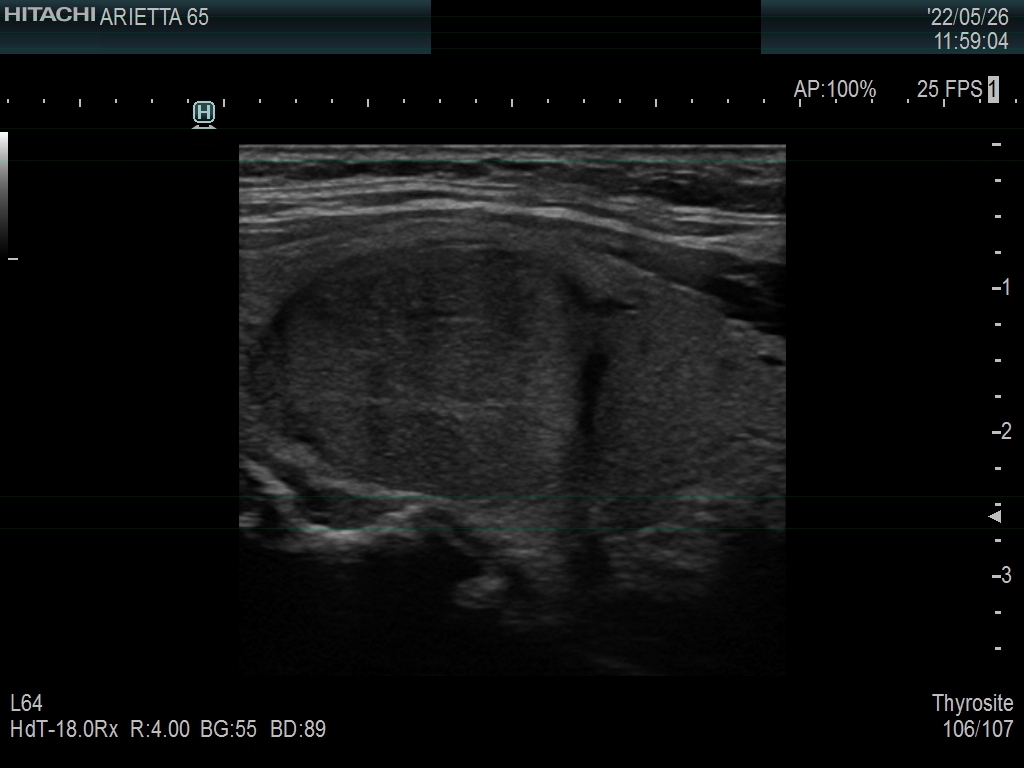

Ultrasonography. The thyroid was echonormal. There was a moderately hypoechoic nodule in the right lobe. The nodule has halo and presents with a combined perinodular and intranodular blood flow. The latter was irregularly increased.

The presentation of the nodule is not very suspicious. Halo sign is a rare finding in medullary cancers.

The classification of the nodule depends on the judgement of nodule borders. If it is regarded as irregular, then the lesion is an EU-TIRADS 5 one. However, if we judge the borders as non-lobulated, then the lesion is an EU-TIRADS 4 nodule. According to the EU-TIRADS, FNA is indicated in both cases because the largest diameter of the nodule exceeds 15 mm.